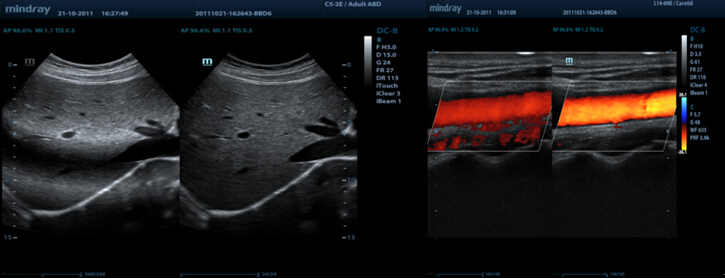

Auto IMT (Intima-Media Thickness)

Automatische meting van anterior en posterior wanddikte voor een nauwkeurige statusbepaling van de arteria carotis

iTouch?

Voor directe automatische beeldoptimalisatie in B-, kleuren- en PW-modus met ├®├®n toetsklik